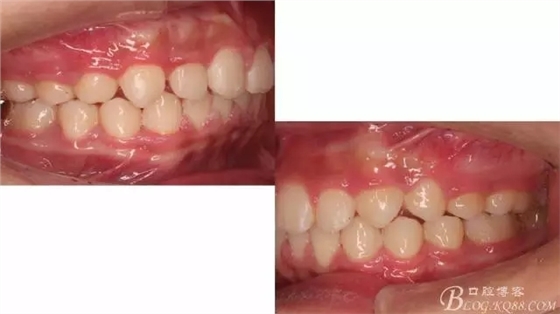

640.webp (1).jpg

640.webp (2).jpg

術(shù)前側(cè)貌,下合后縮還算明顯,正面照有點(diǎn)看不出的樣子!